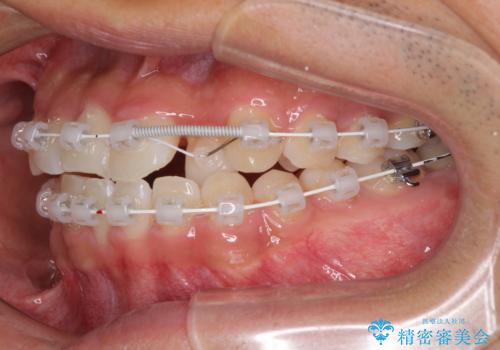

- 矯正装置

- 審美装置

- 治療計画

- 前歯のクロスバイトを気にして来院された患者様です。

美容専門の歯科医院を受診したところ、セラミックでの改善は無理と断られてしまったとのことでした。

歯がすり減って不揃いの形態となっていますが、まずは矯正治療によりクロスバイトを改善することとしました。

治療期間を極力短くしたいとのことで、ワイヤー矯正により治療を行うこととしました。